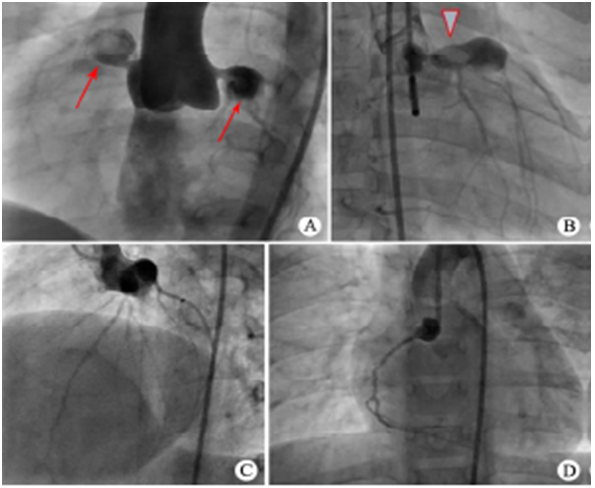

CoronaryAngiography (冠状动脉造影)

左、右冠状动脉巨大冠脉瘤伴血栓形成

左前降支巨大冠脉瘤内有血栓,远端狭窄

回旋支冠脉瘤

右冠脉巨大冠脉瘤伴狭窄